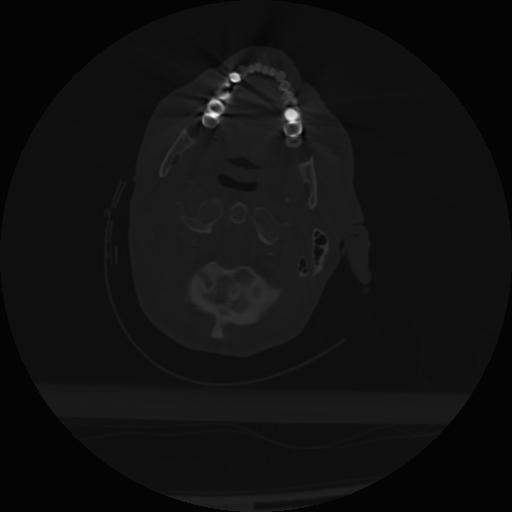

22 ANGIO,CE,Vol,0.5,ANGIO,,